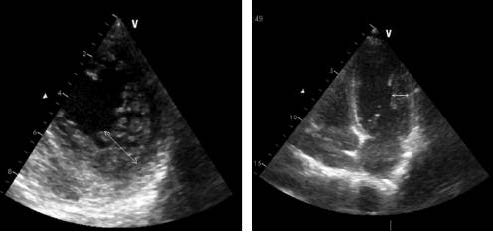

Результаты эхокардиографии (ЭхоКГ) на 2-е сутки: миокард желудочков не утолщен (толщина стенок по 7 мм). Гиперкинезия базальных сегментов всех стенок ЛЖ, выраженная гипокинезия срединных сегментов, акинезия верхушки ЛЖ (рис. 3). ФВ, рассчитанная методом Симпсона, – 45%. Отмечается избыточная трабекулярность миокарда ЛЖ, нельзя исключить некомпактный миокард ЛЖ. Клапанный аппарат без значимых изменений (см. рис. 3).

Рис. 3. ЭхоКГ на 2-е сутки из апикального доступа, левый желудочек: а – диастола; б – систола. Белые стрелки – зоны гипокинезии срединных сегментов.